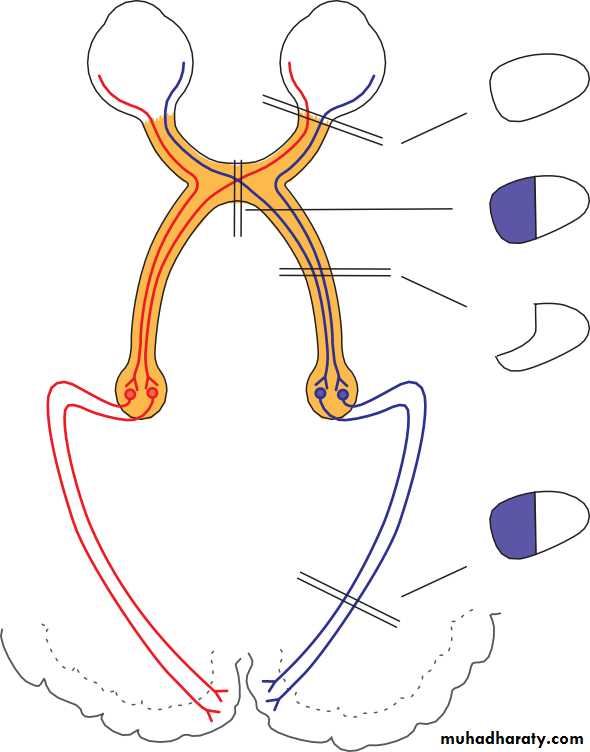

• In a patient in whom the pupil sizes are equal, the next step is to look for a defect in optic nerve function, using the ‘swinging flashlight test’. This is a sensitive index of an afferent conduction defect. The patient is seated in a dimly illuminated room and views a distant object. A torch is directed at each eye in turn while the pupils are observed. A unilateral defect in optic nerve conduction is demonstrated as a relative afferent pupil defect (RAPD) (see Fig. 2.4).

• TEST FOR RAPD

• (a)

• Left eye

• Right eye

• Optic nerve damage

• (b)

• Fig. 2.4 The relative afferent pupillary defect. The left optic nerve is damaged.

• (a) A light shone in the right eye causes both pupils to constrict. (b) When the light is moved to the left eye both pupils dilate because of the lack of afferent drive to the light reflex; a left relative afferent pupillary defect is present. Opacity of the ocular media (e.g. a dense cataract), or damage to the visual pathway beyond the lateral geniculate body will not cause a relative afferent pupillary defect.